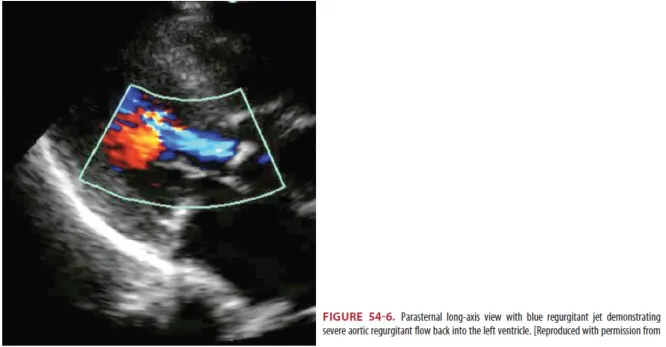

(1) 심초음파